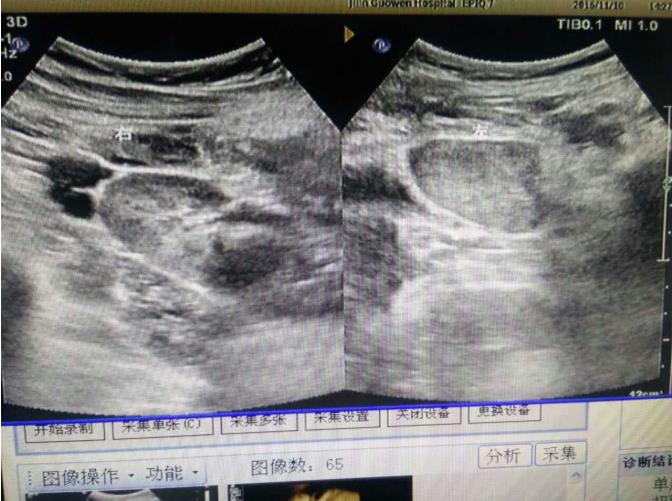

為該患常規(guī)檢查臍帶入口時(shí)發(fā)現(xiàn)臍帶入口位于胎盤下緣邊緣,胎兒超聲檢查無陽性發(fā)現(xiàn)。常規(guī)掃查右卵巢時(shí),發(fā)現(xiàn)右卵巢旁可見腎臟回聲(正常情況下,右卵巢旁是不會(huì)掃查到腎臟回聲的),大小、形態(tài)如常,CDFI:腎內(nèi)血流灌注尚可,故囑患者左側(cè)臥位,顯示孕婦右腎位置、大小及形態(tài)正常,囑孕婦右側(cè)臥位,發(fā)現(xiàn)脾臟下方無腎臟回聲,故考慮該患左腎游走腎。該患于2016年12月2日復(fù)查,結(jié)果如前。